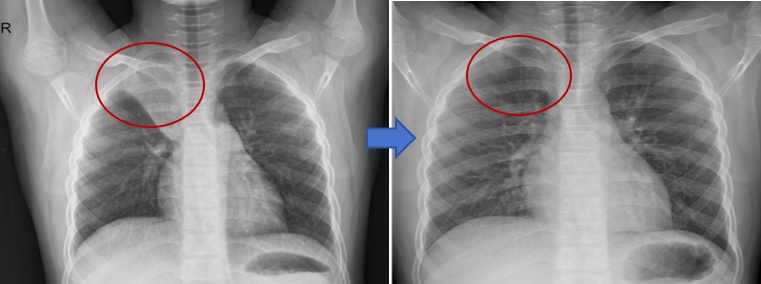

呼吸康复门诊的呼吸专科医生、康复医生、呼吸专科护士共同查阅了小杰近期的肺功能报告和胸部影像。呼吸专科医生对小杰进行了的呼吸肌力、六分钟步行试验等评估,并向小杰妈妈耐心解释道:“小杰的肺部经历了一场重病,要让肺功能恢复到正常状态,还需要借助康复训练来达成。”随后,呼吸专科医生和康复科医生共同为小杰制定了一套详细的呼吸康复训练方案,呼吸专科护士具体指导小杰学习训练方案中的缩唇腹式呼吸、三球式呼吸训练器的使用、有效咳嗽方法以及体位引流等内容(如图1所示),并定期使用微信沟通督查训练。一个月后,小杰再次来到呼吸康复门诊进行随访,令人欣慰的是,小杰的各项肺功能指标以及胸部影像较之前都有了明显的好转(如图2、图3所示)

图2:小杰住院前后胸片对比图